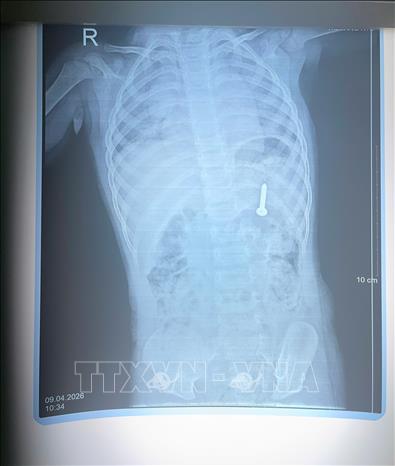

Qua thăm khám và chụp X-quang, các bác sĩ xác định dị vật đã nằm trong dạ dày, có nguy cơ gây thủng đường tiêu hóa và xuất huyết nghiêm trọng nếu không được can thiệp kịp thời. Trước tình huống khẩn cấp, các bác sĩ thuộc các khoa Hồi sức cấp cứu, Nội soi thăm dò chức năng và Gây mê hồi sức đã nhanh chóng hội chẩn liên chuyên khoa, quyết định thực hiện nội soi cấp cứu dưới gây mê.

Phim chụp X-quang của bệnh nhi nuốt đinh vít dài 2,5cm. Ảnh: TTXVN phát